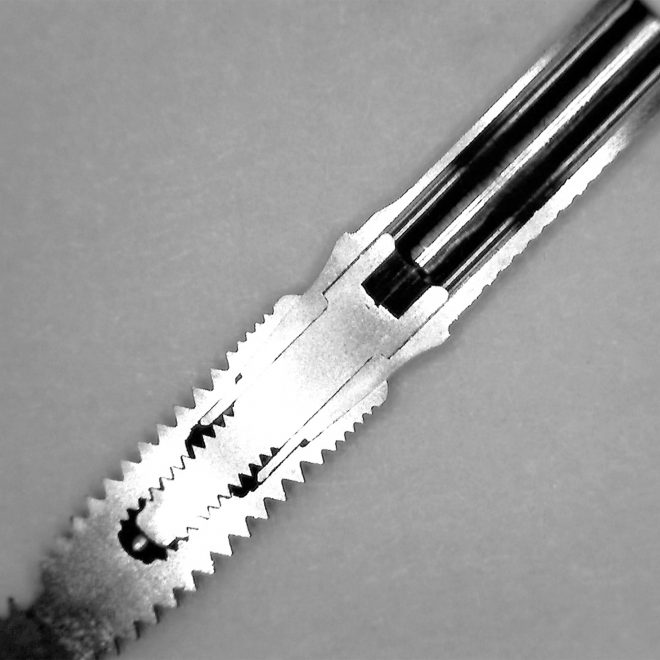

Desde 1985 tenho colaborado com o professor Per-Ingvar Brånemark e nos últimos anos, desenvolvi, juntamente com ele e Christian Brånemark, uma nova macro geometria do ápice do implante. Está parte apical do implante tem a função de reduzir o atrito, devido a seu corte preciso, controlando o torque de inserção, coletando lascas de tecido ósseo para o interior da câmara apical.

“Since 1985 I have been collaborating with professor Per-Ingvar Brånemark and during the last years, I have, together with him and Christian Brånemark, developed a new implant tip.This part of the implant is reducing friction, due to precise cutting, reducing insertion torque and collecting bone chips inside the tip part of”